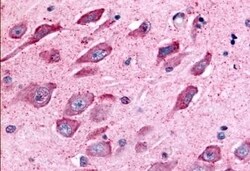

TAOK1 Polyclonal Antibody for IHC (P)

| Immunohistochemistry (Paraffin) | |

| Synthetic 16 amino acid peptide from internal region of human TAOK1. | |